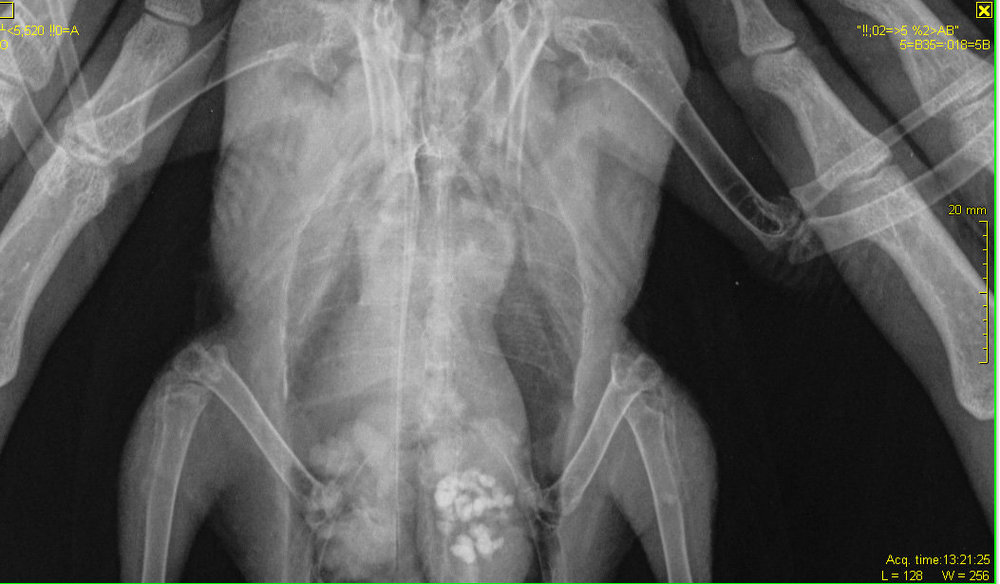

OFA Опубликовано 24 июля, 2021 #3 Опубликовано 24 июля, 2021 @Cara Mia нужно звать Зосю смотреть снимок, но из-за перелома костей предплечья, тем более по снимку без особого смещения, птица так держать крыло не будет, как на фото в коробке. Анализы делали? Помет в микроскоп смотрели? Травма из-за чего, собака/кошка потрепали? Назначение лекарств не совсем понятно, как будто решили всё и сразу полечить( Коробкане подходит для содержания птицы, она слабовентилируемая, нужно дырочки снизу по всему периметру сделать большие и на крышке или по периметру вверху коробки сделать большие дырки Переношу в Лечение голубей

Zosia Опубликовано 29 июля, 2021 #15 Опубликовано 29 июля, 2021 Вам надо сделать еще раз снимок, с аккуратно и полностью раскрытым поврежденным крылом. Фиксировать к основанию (над кассетой) бумажным скотчем, придерживать крыло у плеча. Потому что на вашем первом снимке- полный многооскольчатый перелом локтевой кости с малым смещением, а вот лучевая кость выглядить выбитой (оторванной), что озанчает внутрисуставный перелом...Но т.к. крыло снято не в раскрытом состоянии- степень повреждения оценить трудно. Что там с легкими- а что-то есть- так же плохо видно. С успехом это м.б. микоплазмоз, или клебсиелльная пневмония, или тупо аллергическая реакция на что-то. Глубокий мазок из глотки и помет- и красить по Циль-Нильсену. Смотреть КУМ и криптоспоридии. Ну и банальный общий анализ помета (копрограмма) Пока основная терапия- снятие боли (НПВС), травматин, миорелаксант можно (толперизон). Фиксация - магкая, в сетчатый трубчатый бинт, со свободным здоровым крылом. Вот аткого типа: https://public.fotki.com/Shemlik/bae5/b70c.html https://public.fotki.com/Shemlik/bae5/2.html#media https://public.fotki.com/Shemlik/bae5/3.html#media

Cara Mia Опубликовано 4 августа, 2021 Автор #17 Опубликовано 4 августа, 2021 Добрый день! Снимки нового рентгена голубя были сделаны в клинике "Главное Хвост". Лечащий врач этой клинике после осмотра и на основании этих снимков сделала такую выписку (фото) с диагнозом (диф.) Аэросаккулит, (диф.) Аэроцистит. По перелому сказала, что оба крыла работают, оно начинает срастаться, но необходимо извлечь остатки раздробленной кости, для чего нужна операция, а вывихи вправлять в Беларуси не могут. Посоветовала записаться на прием к главному врачу-орнитологу клиники А. Полозу, который до 14.08. находится в отпуске. Назначены следующие препараты: 1. Амоксициллин 250 мг - внутрь по 1/16 содержимого капсулы 1 раз в день, на протяжении 10 дней. 2. Мелоксидил сусп. - внутрь по 0,1 мл 1 раз в день, на протяжении 10 дней. 3. Нистатин 500000 ед. - внутрь по 1\6 таблетке 2 раза в день, на протяжении 14 дней. 4. Карсил - внутрь по 1/10 таблетки 1 раз в день на протяжении 14 дней. Не входит ли это в противоречие с уже существующим назначением другого врача?: 1. Ципрофлоксацин, 250 мг, внутрь по 1/10 таблетки 2 раза в день 3 недели (ПРОДОЛЖЕН С 14 ДО 21 ДНЯ ПОСЛЕ ПЕРВЫХ СНИМКОВ РЕНТГЕНА) Курс начат 22.07 Курс будет закончен 12.08 2. Мелоксикам 7.5 мг, внутрь по 1/10 таблетки 1-2 раз в день, 7 дней, далее по состоянию Курс начат 20.07 Курс закончен 27.07 3. Метронидазол 250 мг внутрь по 1/8 таблетки 1 раз в день 5-7 дней Курс начат 20.07 Курс закончен 26.07 4. Нистатин 500000 ед. внутрь по 1/4 таблетки 2 раза в день в течение месяца (ДОБАВЛЕН ПОСЛЕ ПЕРВЫХ СНИМКОВ РЕНТГЕНА) Курс начат 22.07 Курс будет закончен 22.08 5. Празицид, суспензия для котят внутрь по 0.3 мл 2 раза с интервалом 14 дней Курс начат 23.07 Курс будет закончен 07.08 6. Стронгхолд 1/2 пипетки 2 раза с интервалом 21 день Курс начат 18.07 Курс будет закончен 07.08 СОСТОЯНИЕ: Голубь стал беспокойным, постоянно пытается выбраться из контейнера, часто машет крыльями. Ест хорошо, по назначению врача (каши, семена подсолнечника, льна), морковь и салат добавляю,но он не ест почти). Несколько дней назад цвет стула изменился на зеленый (фото), врач связала это с большим количеством медпрепаратов. Во время кормления лекарствами через пипетку сейчас вертит головой, оказывает сопротивление (раньше такого не было). Также при приближении руки убегает, вырывается и немного "кряхтит" (так, как это делают утки). Звук могу скинуть, если нужно. На приложенных гифках он сегодня после приема у врача, в состоянии стресса. Также Ахова птушак Бацькаўшчыны (@apb_birdlife_belarus посоветовала мне связаться с Зоей Кенько. Спасибо ей большое, что она сразу же ответила, и помогла с расшифровкой назначений, а также с контактами хороших хирургов и терапевта для проведения операции. АНАЛИЗЫ: На анализы есть возможность записаться в субботу, этого врача советуют консультант Зоя Кенько и Валерия Сороко (ВетТаргет). Стоит ли ждать продолжать курс, менять курс лечения, не дожидаясь анализов (мазок из зоба, копрограмма) до субботы хорошего врача (Вересовая Екатерина)? К сожалению, в других клиниках или не делают эти анализы, или (по отзывам волонтеров и хозяевов) делают их не совсем качественно. Прошу Вас помочь с диагностикой голубка и спасибо большое за помощь! @Zosia @OFA @маленький принц

OFA Опубликовано 7 августа, 2021 #19 Опубликовано 7 августа, 2021 @Cara Mia назначения вполне адекватные, следуйте назначению доктора. Крыло, боюсь, это не вылечит( Висит крыло сильно, скорее всего есть перелом в плечевом суставе, но может и воспаление. Зося смотрела 2 рентген?

Cara Mia Опубликовано 7 августа, 2021 Автор #20 Опубликовано 7 августа, 2021 Зося @Zosia ещё не смотрела. Врач сказала, что кости уже срастаются.

Zosia Опубликовано 8 августа, 2021 #21 Опубликовано 8 августа, 2021 Срастаются. Будет некоторое ограниечение в функционале, но рабочее. А отломок- может и сам отторгнуться, через образовавшийся (в идеале) свищ. Остеогенон проперйте. 1/20 капсулы в сутки, три недели.